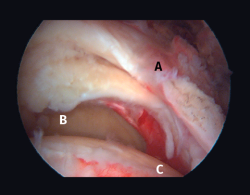

Figura 10. Grado 2 de la clasificación de Patte. A: rotura retraída del tendón supraespinoso; B: glena; C: cabeza humeral.

La clasificación más utilizada para describir la retracción tendinosa es la realizada por Patte, que utiliza la distancia entre el tendón retraído y su inserción original en el troquiter en el plano coronal. El grado 1 describe una rotura con retracción mínima, en el grado 2 el tendón está retraído medial a la huella de inserción, pero no llega a la glena, y el grado 3 representa una rotura retraída a nivel de la glena (Figura 10). Tanto los estudios de imagen como la evaluación intraoperatoria permiten definir una buena estrategia quirúrgica para realizar una buena liberación de las partes blandas y predecir el pronóstico de la reparación(18,19).